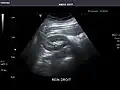

Renal ultrasonography

Ultrasonography of the kidneys is essential in the diagnosis and management of kidney-related diseases. The kidneys are easily examined, and most pathological changes in the kidneys are distinguishable with ultrasound.[7]

Left kidney